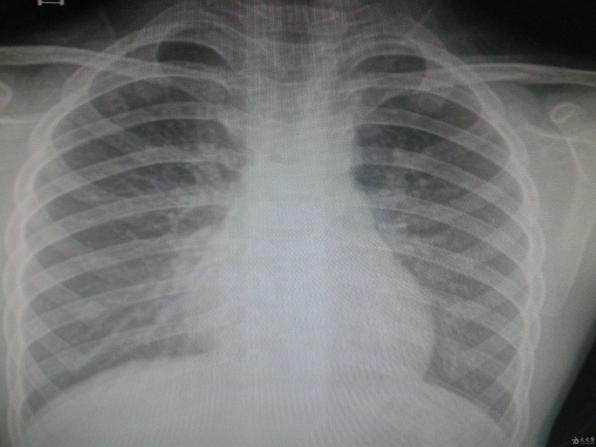

如果不搞一個話我就把你曝光了,以后在發現這個情況我就把你按照胸片曝光出來,你不怕把東西用給我刷,我就把你按到辦,然后還敢等你一。第二張拍的胸片,被醫生將肋骨骨折的部位曝光為白色,隱瞞肋骨骨折的...